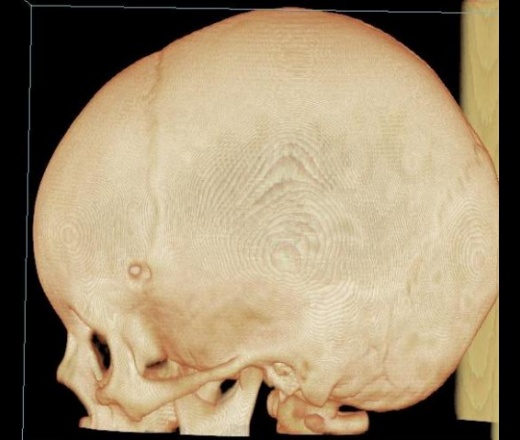

Ребёнок коллеги из нашей больницы, 1 г. 9 мес. С 1,5 месячного возраста отмечали небольшую припухлось в левой теменно-височной области, которая постепенно увеличивалась с ростом ребёнка. Припухлость расценивалась как лимфоузел, однако в связи с длительным характером процесса решили дообследовать. Доктор, выполнявший УЗИ, сообщил, что на лимфоузел это не похоже, и он не видит кости под образованием. Выполнили рентгенографию, затем - КТ.

Наиболее вероятен дермоид. Округлый костный дефект с четкими ровными контурами - атрофия от давления. Дефект в наружной пластике больше, чем во внутренней (блюдцеобразный дефект). Плотность образования вероятно жировая. Локализация на границе швов также более характерна для дермоида. Фибромы гораздо плотнее, вряд ли вызовут атрофию от давления, никогда не слышала о таком, доброкачественным опухолям проще расти кнаружи, чем разрушать кость. Часто фибромы достигают значительных размеров и не вызывают атрофию от давления. Интересно образование плотное или мягкое, четко отграниченное, с гладкой поверхностью?

Безболезненность и плотность образования говорит в пользу дермоида. Контуры нечеткие? А как же сравнения с лимфоузлом? Возможно контуры скрадывают мягкие ткани головы, тем более само образование маленькое. Если КТ делали у Вас, попросите измерить плотность. А контуры дефекта действительно гладкие, подчеркнутые? Я не ошибаюсь? Не очень хорошо видно на КТ, слишком мелко.

Контуры гладкие. Плотность от 14 до 27 HU.

Очень характерна локализация, форма и размеры дефекта. У нас очень часто проходят дети с дермоидами данной локализации, на рентгенограммах определяется атрофия от давления.

Мы пытаемся этим деткам выполнить снимок так, чтоб образование вывести на контур, если получается, то видна вдавленность контура кости (не всегда, правда, получается, потому что все эти детки маленькие, удержать очень сложно). Если будут снимки, покажу. Обычно их забирает хирург, и к нам они не возвращаются. А вот КТ им не делали ни разу, поэтому не знаю, как это выглядит на КТ.

Согласен с версией дермоид; в образовании есть участки низкой плотности сопоставимыми с плотностью жира, что является характерным признаком при дермоидах.

Спасибо, коллеги, за помощь. Похоже, это действительно дермоидная киста.